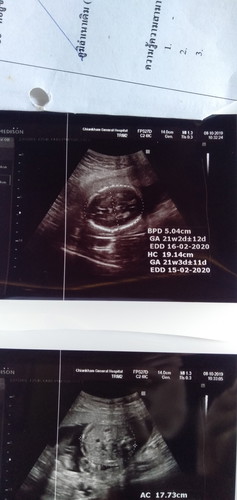

ผลซาวด์

ได้ผุชายน่ะค่ะแม่ น้องปกติดีทุกอย่างค่ะ น้องโตตามอายุครรภ์คุนแม่น่ะค่ะ ตอนนี้หนุอายุได้21w+6dละครับแม่ๆ